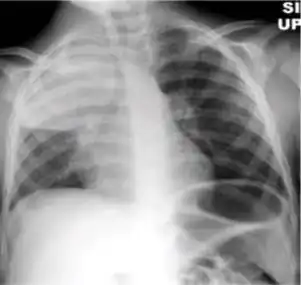

Chest x-ray showing patchy opacification on the upper right and mid-zone lung with fibrotic shadows, as well as bilateral hilar lymphadenopathy. -